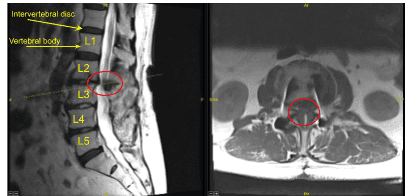

Este paciente había sido sometido previamente a una artrodesis instrumentada en una instalación externa en L3-5. Presentaron dolor en la parte anterior del muslo derecho y en la pierna posterior izquierda. Las imágenes mostraron degeneración de segmentos adyacentes por encima y por debajo de su masa de fusión, lo que correlacionaba bien con sus síntomas.